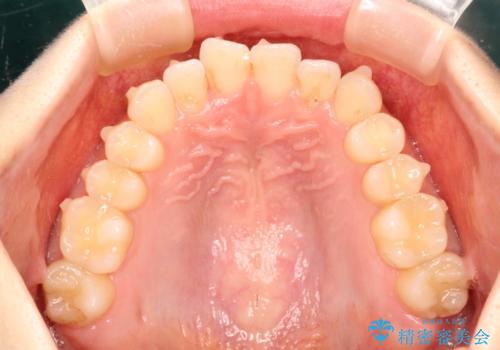

前歯のガタガタをインビザラインで目立たず矯正

- 目立たずに前歯を矯正したいとのことで来院されました。

歯と歯の間にわずかに隙間を作りスペースを確保し、インビザラインにて矯正を行うこととなりました。

前歯の微調整に少し時間がかかりましたが、整った歯並びにすることができました。